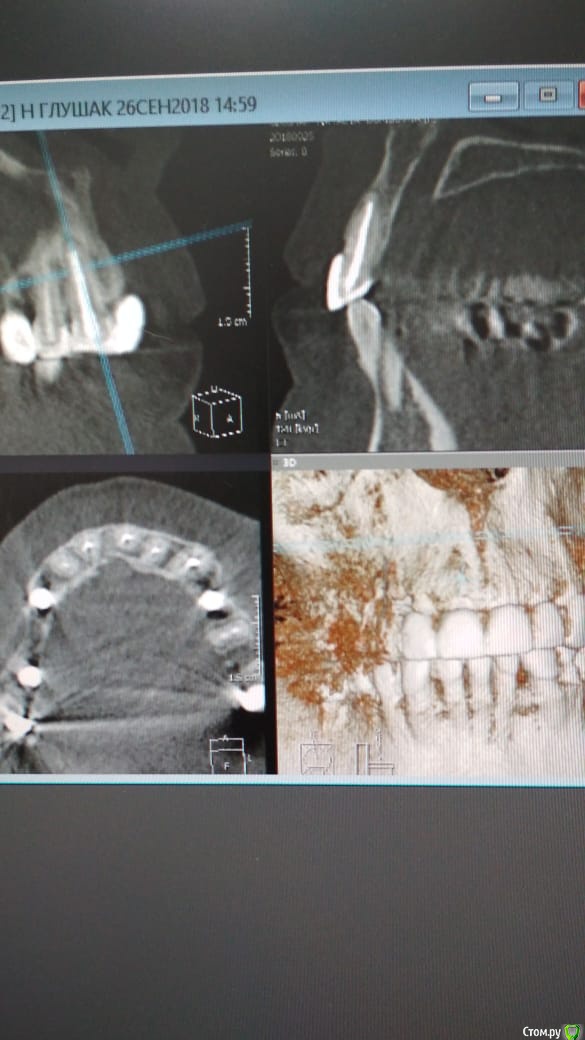

Alexandr_doc Опубликовано 26 сентября, 2018 Автор Поделиться Опубликовано 26 сентября, 2018 Прошу извинить за задержку. Прикладываю срезы со свежего КТ. Поступили предложения о хир удлинении, на мой взгляд это в данной ситуации очень рискованно. Ссылка на комментарий

kramer Опубликовано 26 сентября, 2018 Поделиться Опубликовано 26 сентября, 2018 Может, прозвучит банально, но нет смысла резцы вывести из окклюзии? По КТ плотный контакт с антагонистами Ссылка на комментарий